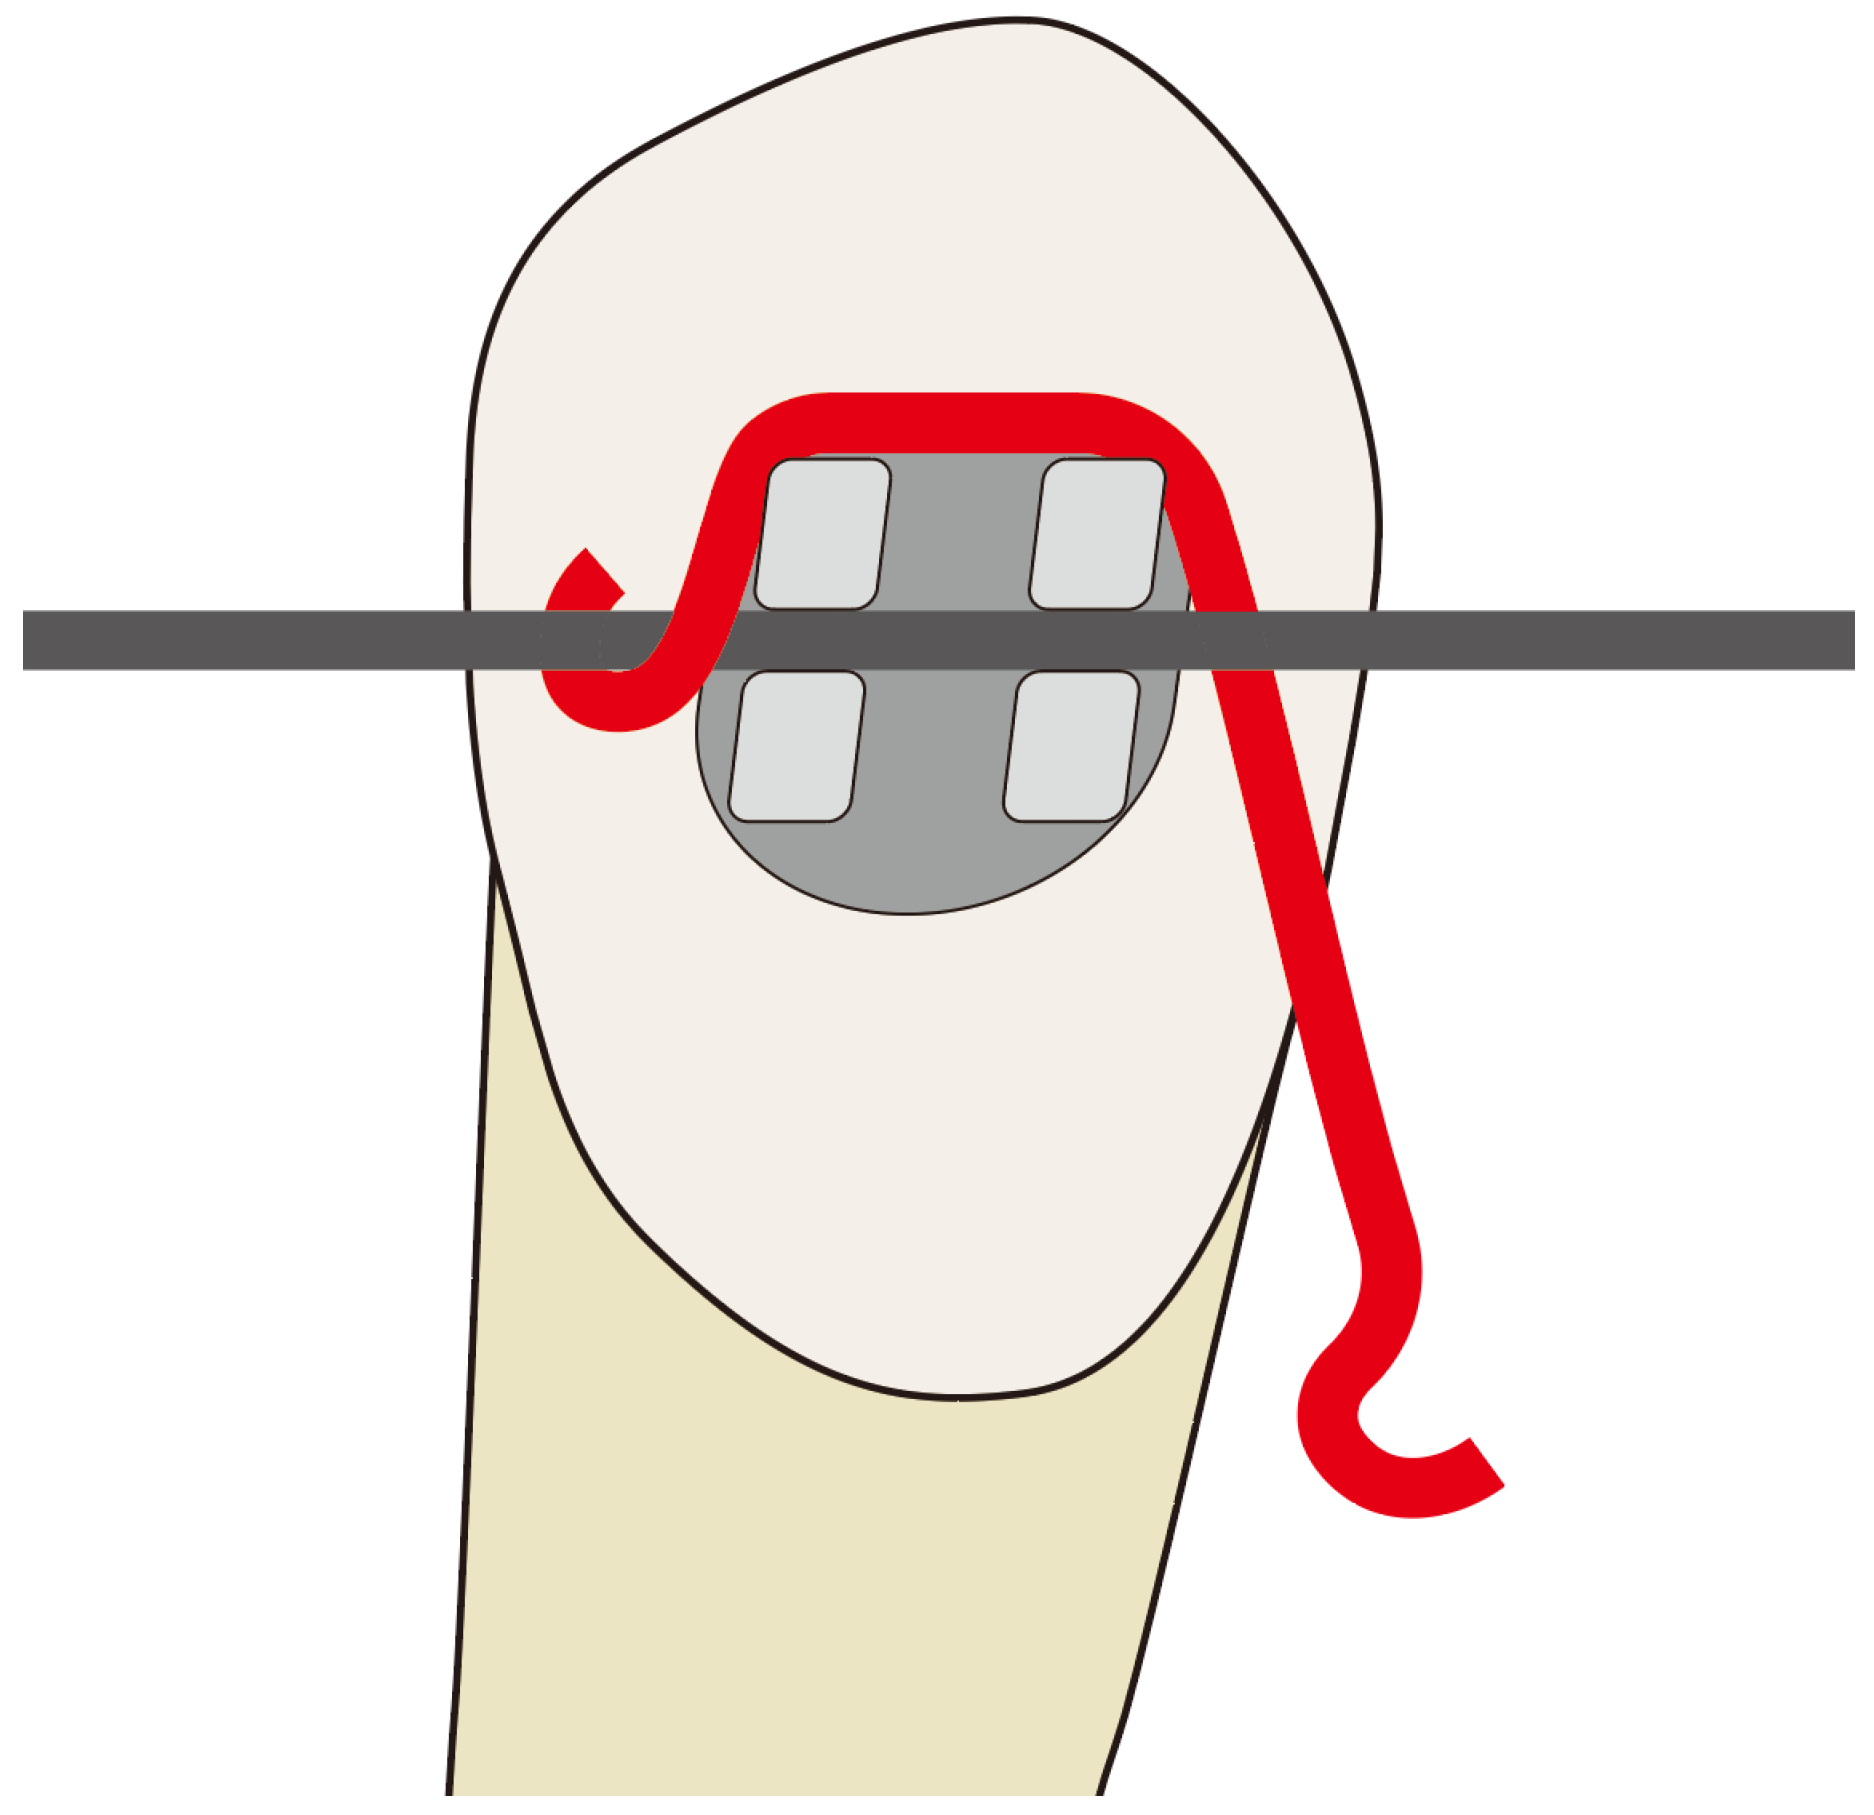

2.1. Fabrication of the Lever Jig

- A model incorporating a lever jig.